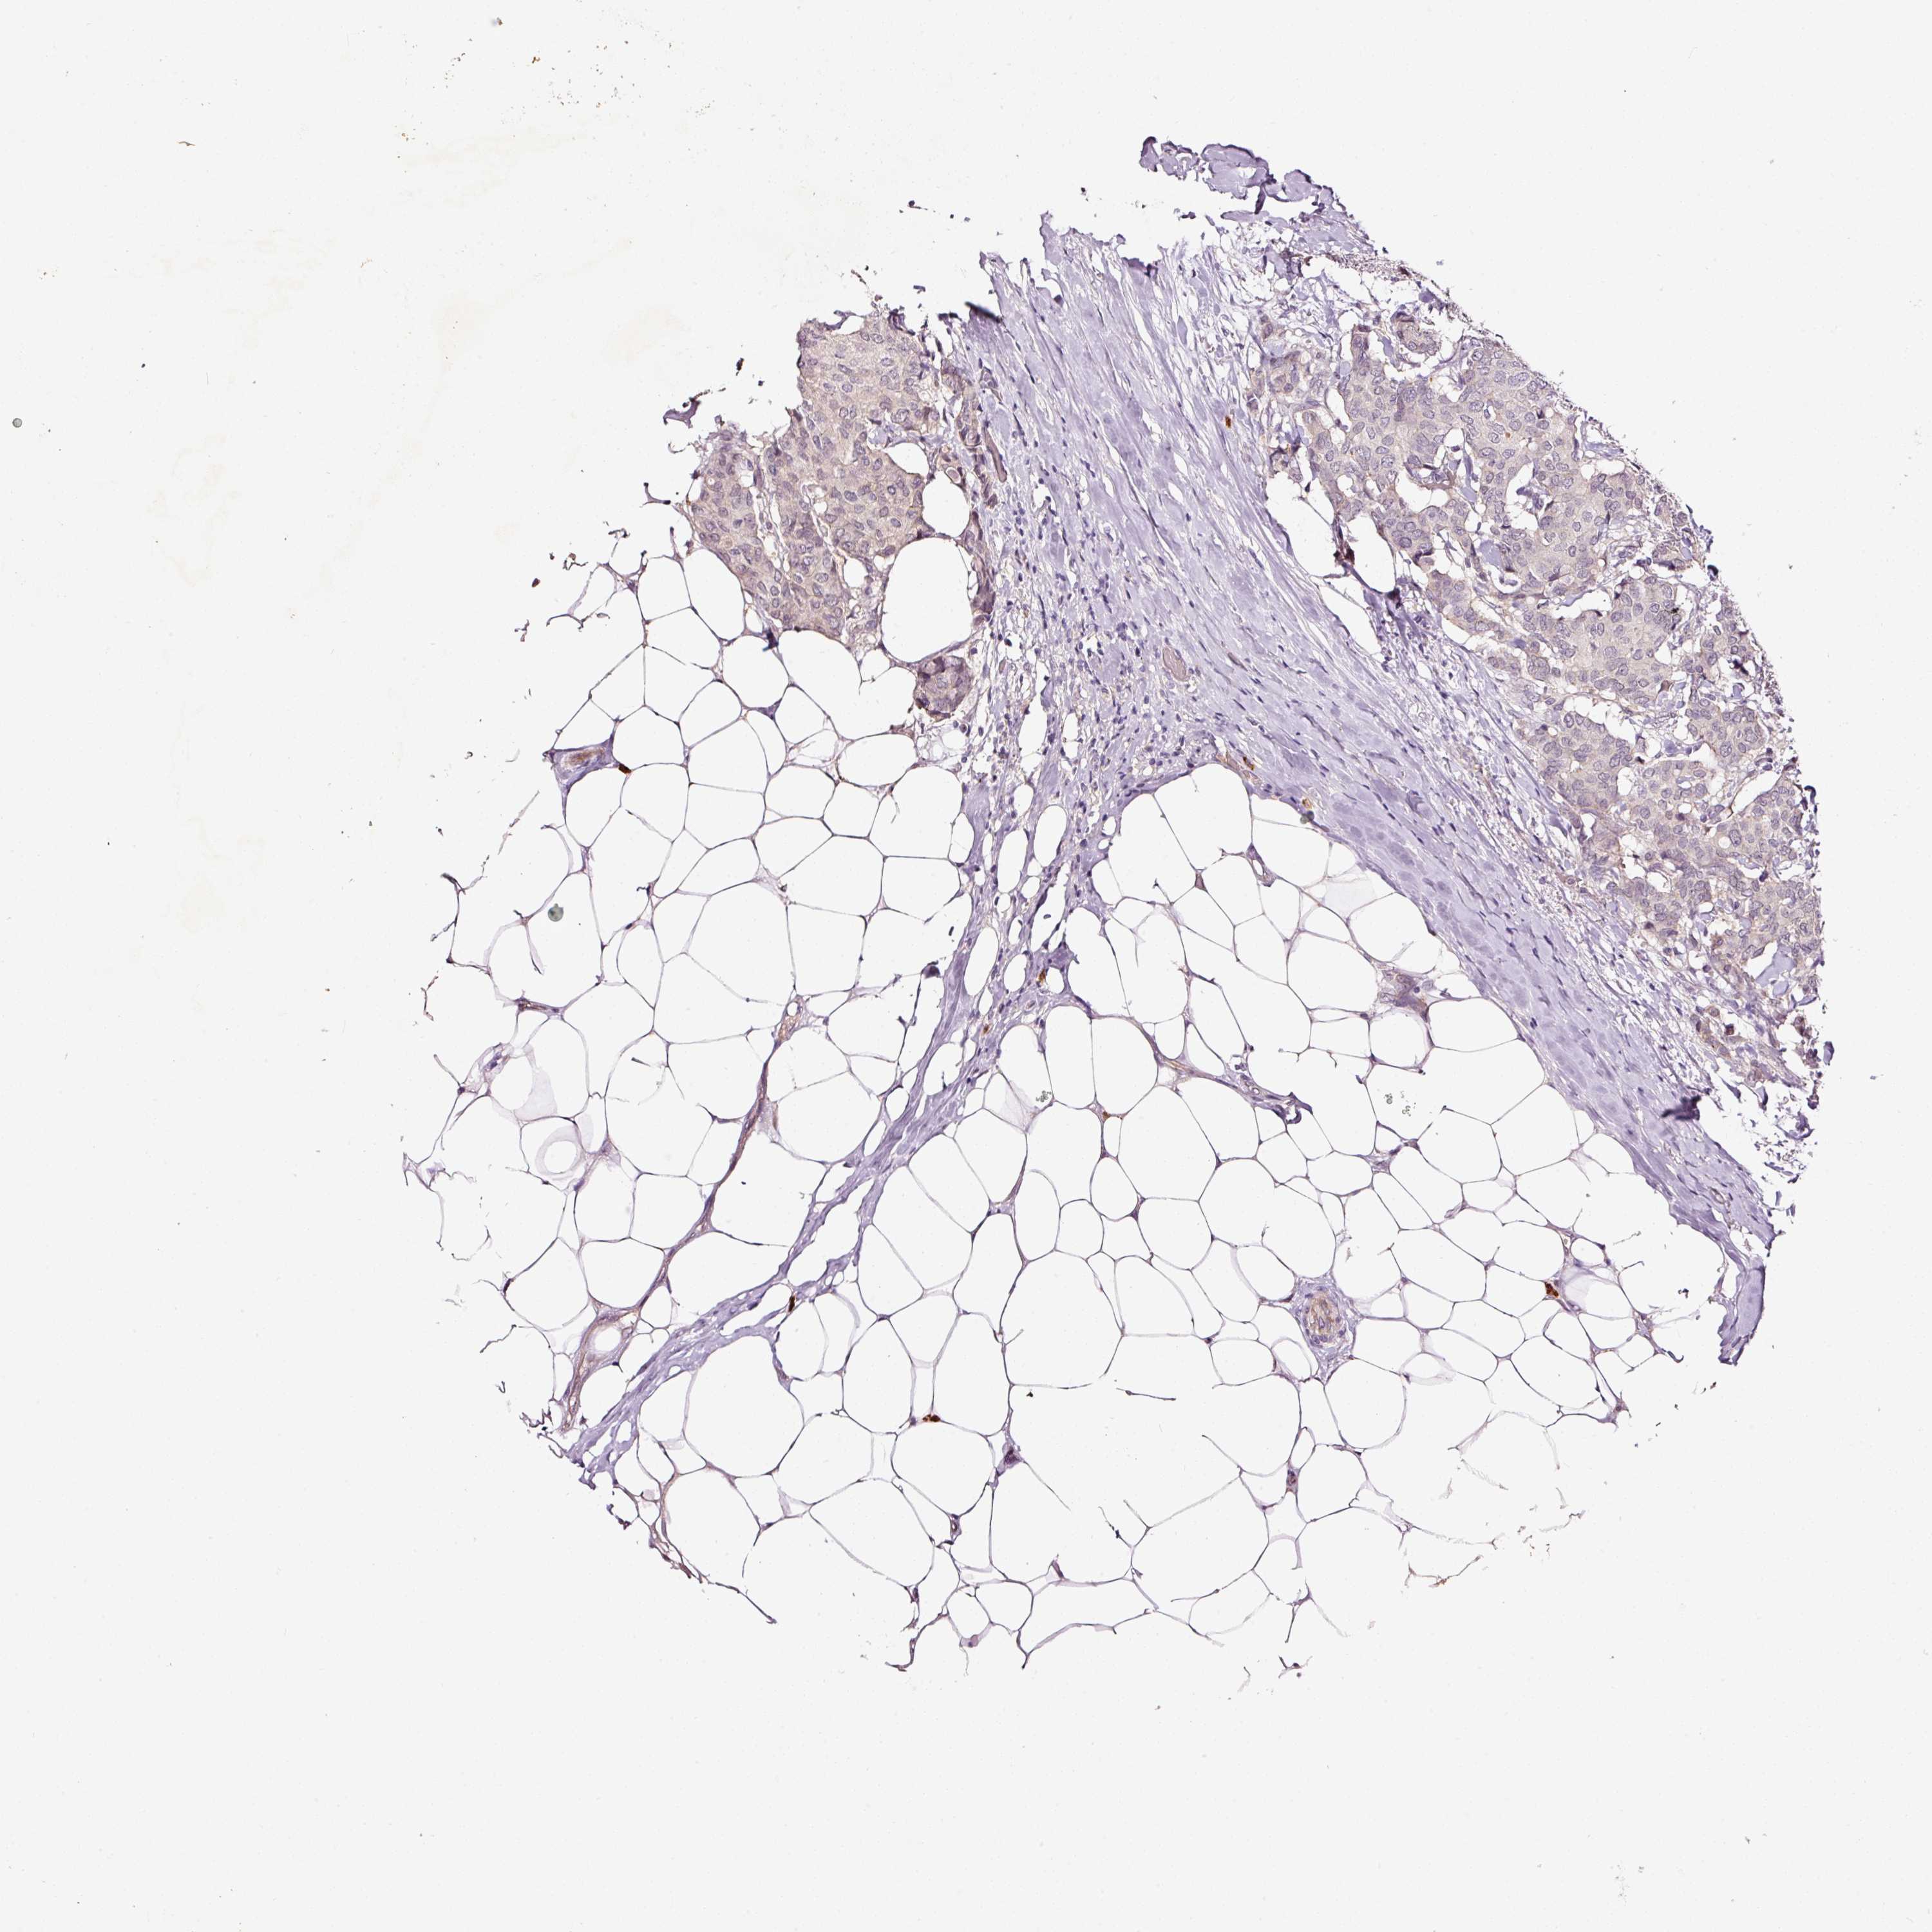

CANCER BREAST CANCER Show tissue menu

BRCA TCGA BRCA VALIDATION PROTEIN EXPRESSION

ANTIBODIES

AND

VALIDATION